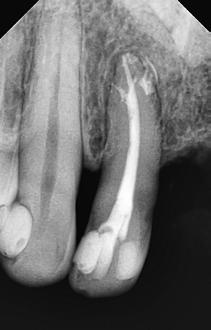

Krell és Caplan kutatásában 2086 repedt fogat vizsgáltak meg. A vizsgált fogak között leggyakrabban a második alsó nagyőrlőfogak (36%), majd ezt követően az első alsó nagyőrlők (27%), és végül az első felső nagyőrlők (18%) fordultak elő. A kutatási eredményeik szerint a fogbél állapota nem befolyásolta jelentős mértékben a kezelés várható kimenetelét. (Irreverzibilis pulpitis 85%; necrosis 80%; korábban gyökérkezelt 74%). A kimenetel szempontjából ugyanígy indifferens volt a páciensek neme, életkora, a kezelés időpontja, a fog pozíciója, a fog helyreállítása során használt anyag típusa, valamint az érintett fogfelszínek száma. 2014 júliusában egy 45 éves hölgy páciens azzal a panasszal kereste fel a rendelőnket, hogy nagyjából 10 napja egy fájdalmas duzzanat alakult ki a jobb felső első kisőrlője koronája mellett (14). A klinikai vizsgálat során egy amalgámtömést találtunk a panaszos fogban. A tömés széli zárása nem volt megfelelő, a disztális záróléc és a tömés között rést tapasztaltunk. A fog disztobukkális és linguális felszíne mellett 8 mm-es csontos tasakokat mértünk. A periapikális felvételen az 14-es foggyökér disztális felszínének megfelelően vertikális irányú radiolucens felritkulást észleltünk. A klinikai vizsgálat során a mesiális zárólécet kettéválasztó törésvonalat detektáltunk (17–18. ábra). A fogszenzibilitás vizsgálata során negatív eredményt kaptunk. A páciensnek ismertettük az elérhető terápiás lehetőségeket: 1, a 14-es fog eltávolítása, majd a foghiány 3 tagú cementezett híddal történő pótlása; 2, a 14-es fog eltávolítása, kemény- és lágyszöveti augmentáció, majd implantátum behelyezése; 3, a 14-es fog gyökérkezelése, gyökértömése és ezt követően a csücsökborítást biztosító restaurátum készítése. Arra is felhívtuk a páciens figyelmét, hogy a 3. terápiás lehetőség választása esetén nem tudjuk a fogmegtartás sikerességét garantálni, de végül – főként anyagi okok miatt – mégis ezt a terápiás opciót választotta. Fontos megjegyezni, hogy a repedt fogak ellátási lehetőségeit a törésvonal mélysége, elhelyezkedése, lefutása nagyban befolyásolja. A kezelés megtervezése során a fog és a fogat körülvevő szövetek állapotával kapcsolatos számtalan különböző faktort kell egyidejűleg figyelembe vennünk. A gyökérkezelést követően a gyökértömést meleg vertikális kondenzációs technikai alkalmazásával készítettük el (19. ábra). A hozzáférési nyílást folyékony és hibrid kompozit tömőanyag segítségével zártuk. A zárás elkészítése során a dr. David Clark által kifejlesztett Bioclear matricarendszert alkalmaztuk. A 6 éves kontroll során készített (2020) röntgenfelvételen a csontos defektus telődése volt megfigyelhető. Ez is a parodontális defektus gyógyulását igazolta (20–21. ábra).

17. ábra: A 14-es fog gyökerének disztális felszíne mellett vertikális csontpusztulásra utaló jelek észlelhetőek. Klinikailag ezen a területen 8 mm mélységű tasakmélységet mértünk. – 18. ábra: A 14-es fog disztális zárólécének megfelelően törésvonal észlelhető, ugyanakkor a csücskök teljes szeparálódására utaló jelek nem láthatóak. Az amalgámtömés eltávolítását követően jól megfigyelhető volt a törésvonal teljes lefutása. – 19. ábra: A gyökértömés elkészítése során meleg vertikális kondenzációs technikát alkalmaztunk. A felvételeken oldalcsatornák jelenlétére utaló jelek is észlelhetőek. – 20–21. ábra: A 2020-ban készült kontrollfelvételeken jól látható a csontos defektus telődése. A radiológiai jelek alapján (jól lekövethető gyökérhártyarés) a parodontális ligamentumok regenerációját is vélelmezzük.

A kezelés megtervezése során a fog és a fogat körülvevő szövetek állapotával kapcsolatos számtalan különböző faktort kell egyidejűleg figyelembe vennünk. Az Amerikai Endodonciai Társaság (American Association of Endodontists) vonatkozó ajánlása azt javasolja, hogy ezekben a helyzetekben mindig vegyük figyelembe az esetspecifikus lokális és szisztémás tényezőket. Ez magába foglalja a páciensek igényeit és kívánságait, az anyagi lehetőségeit, az esztétikai tényezőket, a lehetségesen előforduló szövődményeket, valamint az ilyenkor felmerülő etikai kérdéseket. Az általunk elvégzett kezeléseknek mindig lehető legnagyobb mértékben kell a páciensek érdekeit szolgálni. (www.aae.org/treatmentoptions)